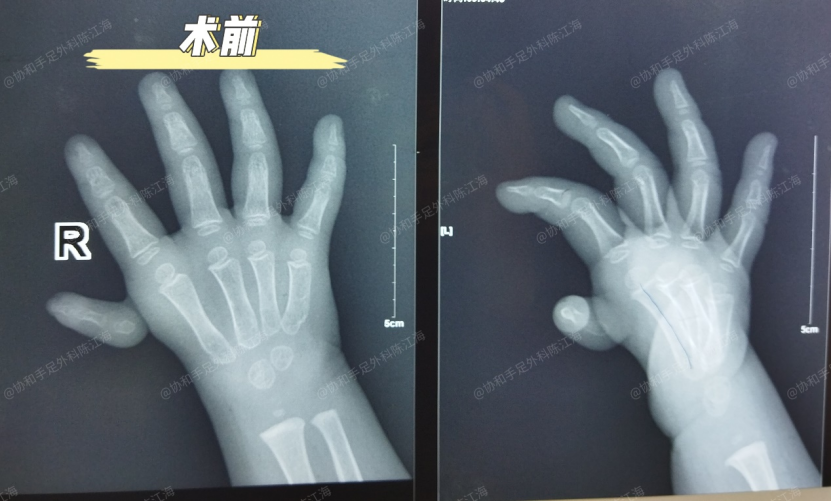

Това момиченце от Шанси вече е на 3 години и на 7 месеца. Дясният й палец беше хипоплазия от палец от тип IV - целият палец беше свързан само към дланта от малък педикул на кожата и беше неподвижен. Това беше една от по -тежките форми на плаващ палец.

През март миналата година извършихме успешна реконструкция на частична метакарпална трансплантация (реконструкция на плаващ палец на SMRT), запазвайки всичките пет пръста. По време на това последващо посещение палецът й е силен - тя няма проблеми с писането, прищипване на малки предмети или усукване на играчки.

Операцията се извършва на два етапа. На първия етап се събира частичен втори метакарпал за реконструкция на първия метакарпал. Вторият етап включва прехвърляне на сухожилие за възстановяване на функцията на палеца. Двата етапа са на разстояние около 3,5 месеца.